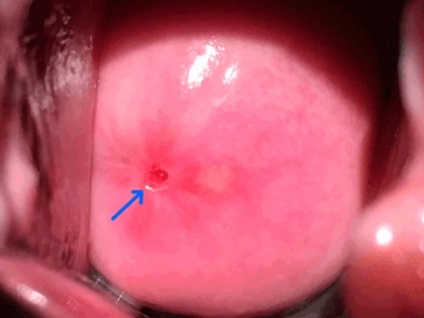

nyálka

nyaki ciszta - a fenti képen látható - lehet csatolni váladékot a helyén a sérülés és gennyes gócok.